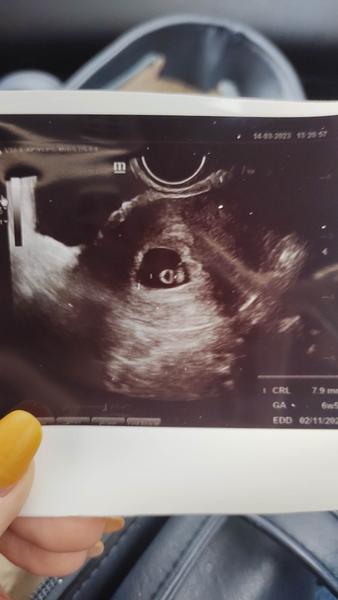

@eveline88 ahoj všetko ok už som videla aj bábo aj srdiečko ako bije som sa tam rozplakala 😅 nieje to malo neboj budúci týždeň keď tak si urob ešte jeden..ja som si robila týždeň na to

@eveline88 8mm srdiečko bije ❤️